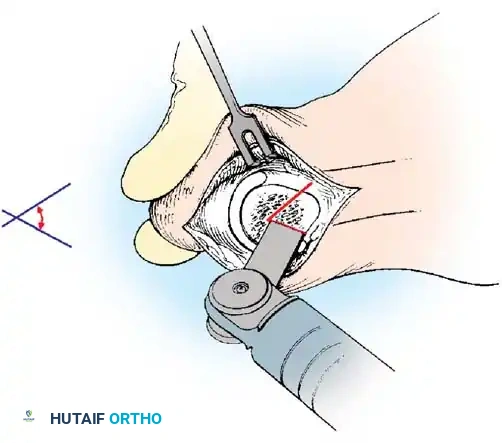

Fig. 78-8 A, Determination of position of articular surface of metatarsal head in relation to longitudinal axis of fi rst metatarsal. B, Measurement of distal metatarsal articular angle at time of surgery. Markings are at medial and lateral margins of articular surface of fi rst metatarsal head and longitudinal axis of fi rst metatarsal shaft. metatarseum between the bases of the fi rst and second metatarsals might preclude the effectiveness of a soft-tissue procedure alone to provide suffi cient correction of the increased intermetatarsal angle. Likewise, accessory sesamoids and prominent ungual tuberosities at the interphalangeal joint contribute to a painful callus at the tibial side of this joint. An os tibialis externum frequently is associated with excessive hallux valgus interphalangeus. Varus of the fi rst metatarsal might be a signifi cant part of the overall deformity of the foot even with an intermetatarsal angle of less than 10 degrees. Metatarsus varus with a relatively small hallux valgus angle (15 to 20 degrees) may produce signifi cant deformity even though the angles are not excessive. The usefulness of computer-assisted compared with manual measurement of the intermetatarsal angle, hallux valgus angle, and distal metatarsal articular angle is still uncertain. Both methods have closer interobserver and intraobserver correlation in measurement of the intermetatarsal angle and hallux valgus angle than in measurement of the distal metatarsal articular angle. The reliability of either method has such a wide range (5 degrees), however, that measurements of these angles, although useful as a guide, do not provide a completely reliable indication of the magnitude of deformity. Condon et al. suggested that the reliability of the intermetatarsal angle can be improved by careful technique and by making the measurements at least twice and averaging them. Schneider et al. reported two methods of determining angular measurements based on distinctly different reference points: (1) a longitudinal axis of the fi rst metatarsal using middiaphyseal reference points, and (2) a center-head technique using a center head (center of the articular surface) and center base

Fig. 78-11 Location of reference points for fi rst and second metatarsals are between 1 and 2 cm from distal articular surface and proximal articular surface of each metatarsal. Because of shorter length of hallux, reference points are placed between 0.5 and 1 cm from proximal and distal articular surface of proximal phalanx. (From Coughlin MJ, Saltzman CL, Nunley JA II: Angular measurements in the evaluation of hallux valgus deformities: a report of the ad hoc committee of the American Orthopaedic Foot and Ankle Society on angular measurements, Foot Ankle Int 23:68, 2002.) support and the medial capsule acting as a spring on stretch. Osteotomy usually is indicated in patients with this medial wedged opening of the joint. If a fi rm forefoot wrap reduces the intermetatarsal angle to a normal value and decreases the hallux valgus angle, however, while congruously rotating the base of the fi rst metatarsal on the medial cuneiform without levering the joint open medially, the McBride procedure can correct the deformity. Correction is improved by excision of the fi bular (lateral) sesamoid because the adductor hallucis and lateral head of the fl exor hallucis brevis are released, markedly reducing the valgus moment at the fi rst metatarsophalangeal joint. In addition, the pull of the fi bular sesamoid on the fl exor hallucis longus through its tendon sheath and pulley system is prevented, reducing another important valgus-producing force on the hallux at the metatarsophalangeal joint. If the fi bular sesamoid is excised, the medial capsule should be repaired with the hallux held in 10 to 15 degrees of valgus. This position must be maintained by a postoperative dressing for 3 or 4 weeks.